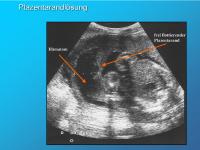

Plazentarandlösung

Abbildung 7

Keywords: BlutungPlazentalösung